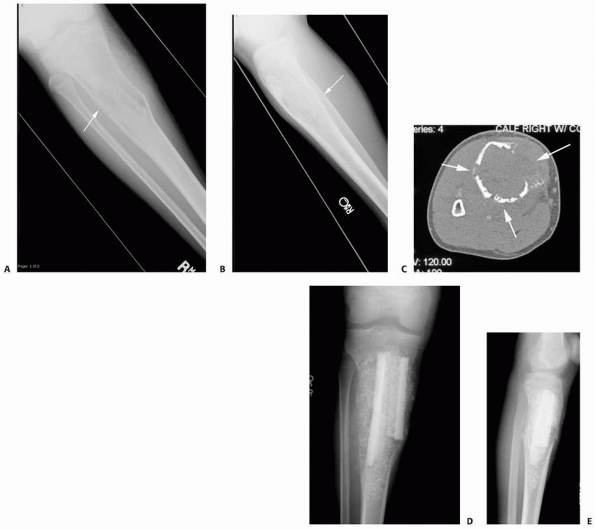

FIGURE 6-3 A 10-year-old boy presented with arm pain after low-energy trauma, 5 days prior. Anteroposterior (A) and lateral (B) radiographs of the right humerus show a nondisplaced pathologic fracture (A–arrow)

through a lytic lesion in the proximal humerus. The lesion is difficult to visualize and the periosteal reaction is also of concern (B–arrow). T2-weighted MRI images show a well-defined, fluid-filled cystic lesion, with fluid-fluid levels (D–arrow) and no soft tissue mass or other worrisome signs in the coronal (C) and axial (D) cuts. The diagnosis was consistent with unicameral bone cyst and conservative treatment was recommended. (Figures reproduced with permission from The Childrens Orthopaedic Center, Los Angeles, CA.) |